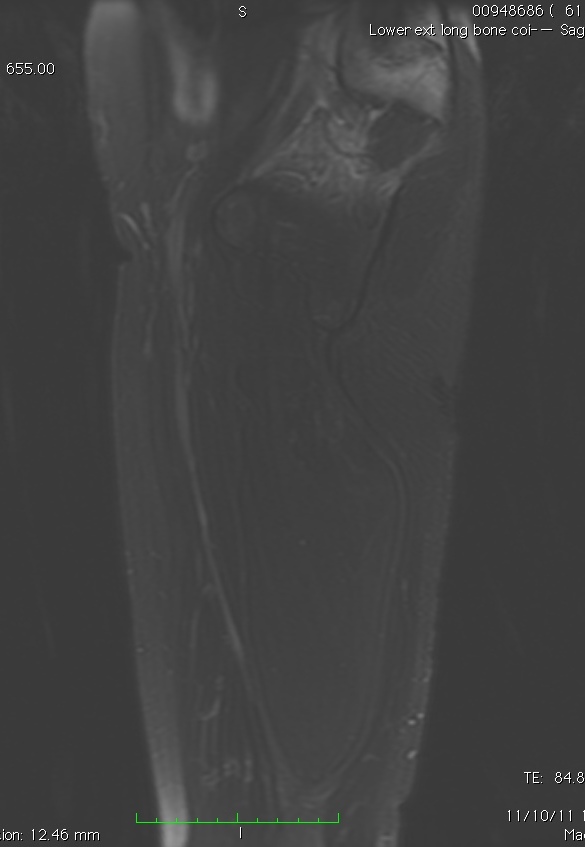

MRI

• Follows the signal characteristics of subcutaneous fat on all sequences

• T1: High Signal

• T2: Intermediate Signal; Low Signal with Fat Suppression

• Minimal or No enhancement with gadolinium

Fig. 1A, 1B, 1C, 2A, 2B, 2C: MRI of a lipoma: T1- weighted images shows an homogeneous mass in the posterior compartment of the thigh with high signal, saturates on fat saturated sequences with no or minimal enhancement. On T2-weighted images demonstrate an intermediate signal on FSE T2, saturates (becomes dark) on fat saturated sequences.